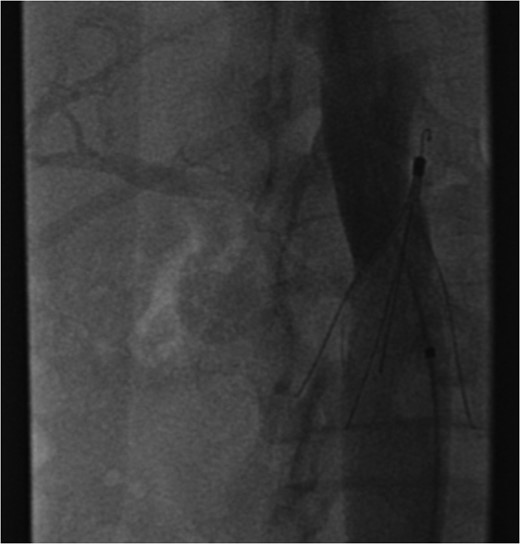

A coronal section of a venous phase abdominal CT demonstrating the end of the IVC filter strut penetrating the wall of the third part of the duodenum.

The patient's coagulopathy was treated and she underwent a laparotomy and evacuation of a large duodenal haematoma. After division of adhesions, a tense duodenal wall was revealed with splitting of the serosal layer. A large haematoma, of about 500 mls volume, was removed from the subserosal layer without breach of the muscularis. The penetrating strut of the IVC filter was able to be palpated within the duodenal wall but was not on view after haematoma removal. There was considerable inflammation of the retroperitoneum as well as scarring from the previous arterial bypass surgery. There was no contamination of the peritoneum with bowel contents. It was thought preferable to remove the IVC filter via the transvenous route rather than expose the IVC and risk large blood loss and arterial graft contamination in the event of duodenotomy.

Excessive tilting of the IVC filter causes the hook of the filter to appear outside of the lumen of the IVC.